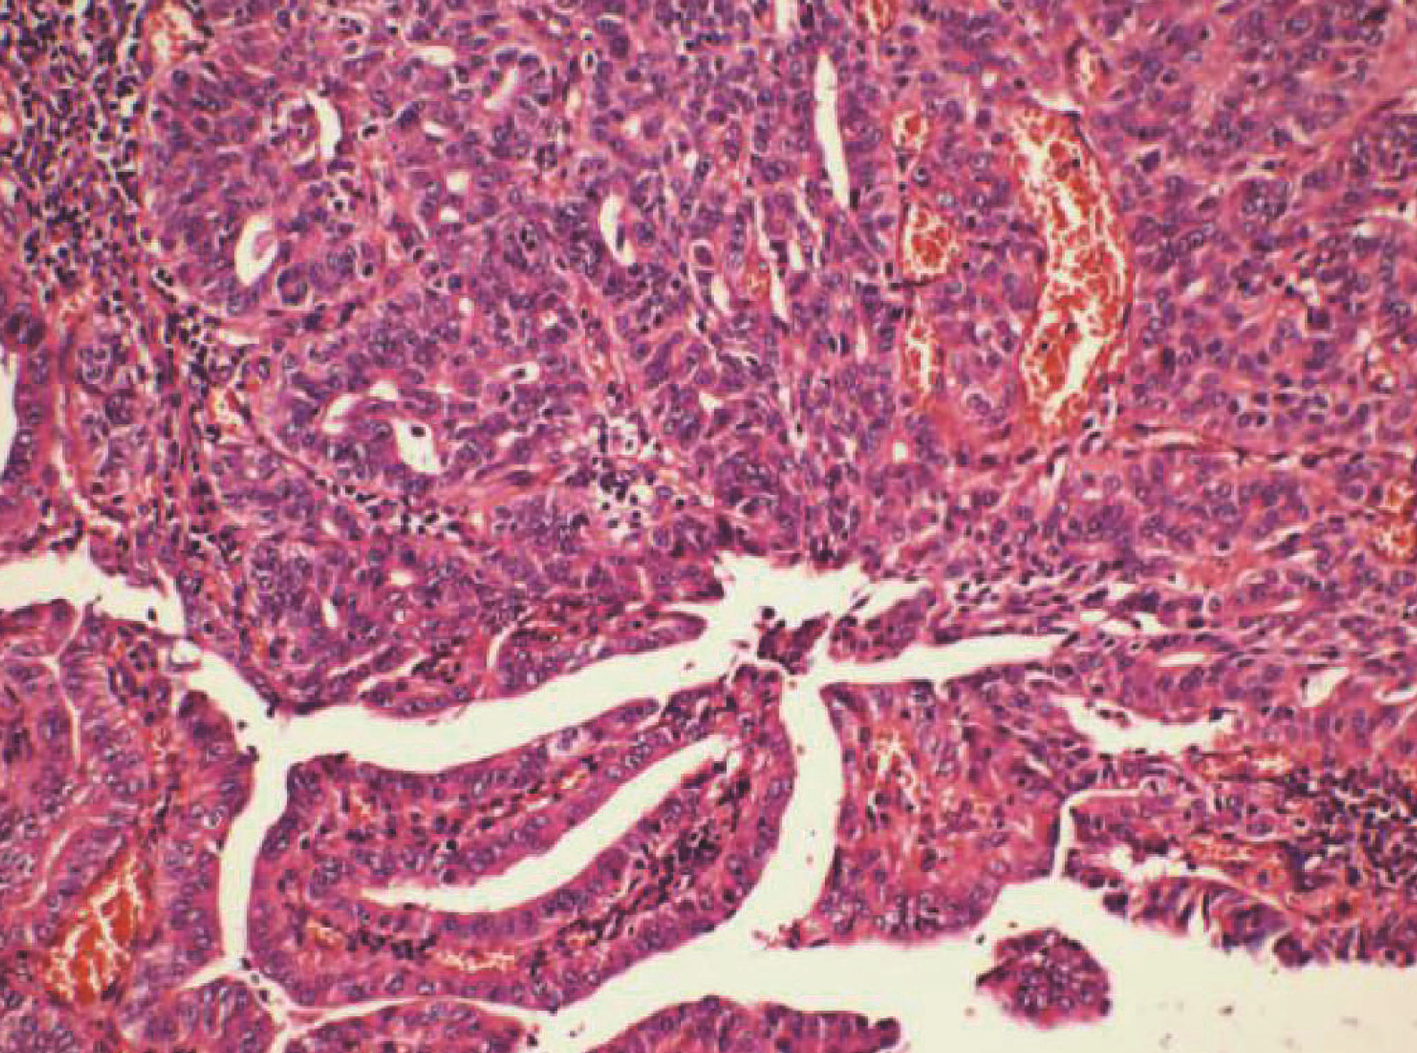

Hepatic paragonimiasis diagnosed by liver histopathology: A case report

Yang LIU, Zhaoxia LI, Tong WU, Jiahe SHI, Ge YU, Guijie XIN

2022, 38(5): 1116-1118. DOI: 10.3969/j.issn.1001-5256.2022.05.027

Abstract(846) HTML (456) PDF (2302KB)(53)

Abstract: